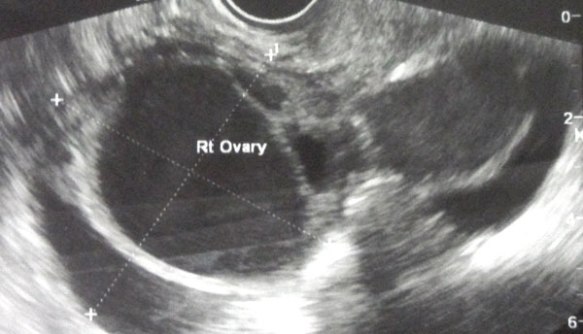

1. Scan in India in June 2011, showed bilateral ovarian cysts.

Right ovary: mass about 4.7 x 8.4 cm with both solid and cystic components seen. Ovary not seen separately.

Left ovary: mass about 8.5 x 5.2 cm with both solid and cystic components and ovary could not be visualised separately.

left-ovary